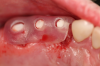

Fig 22. 12 weeks postoperatively.

Figure 22

Sutures were removed 2 weeks after surgical implant placement, and the patient was instructed to continuously wear his Essix-style retainer for 12 weeks. The retainer was worn while eating during the 12-week period. The patient returned at 12 weeks for soft-tissue and implant-bone evaluation (Figure 22). At this appointment, minimal lingual soft-tissue manipulation was performed by gingival abrasion to the keratinized soft tissue and an aluminum chloride gel was placed.